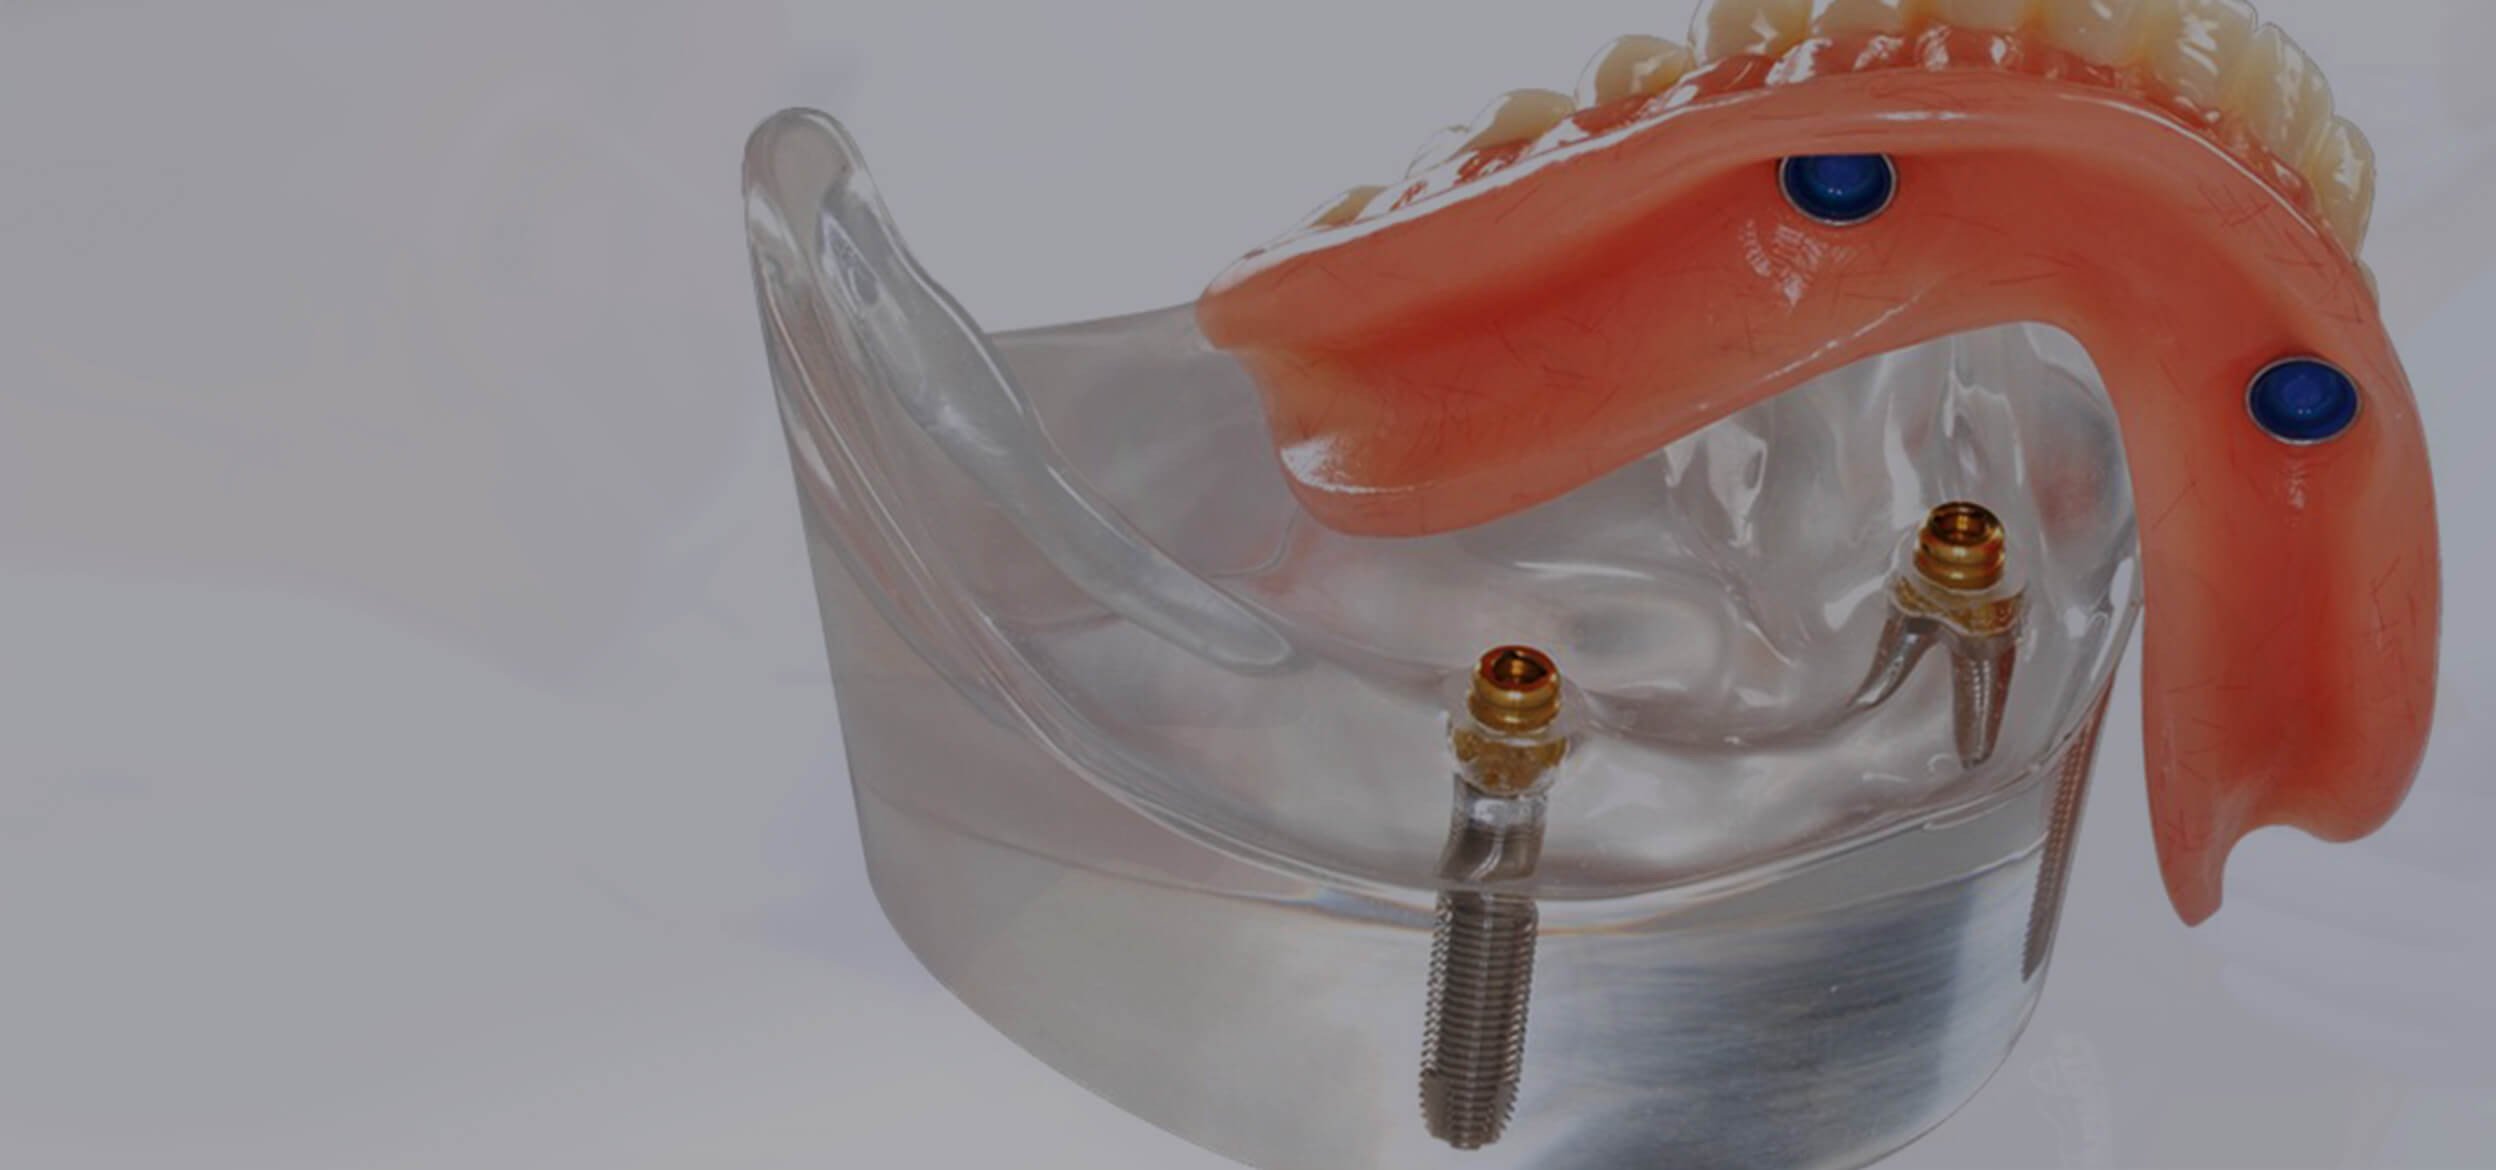

Современные съемные протезы на локаторах: Фото и примеры